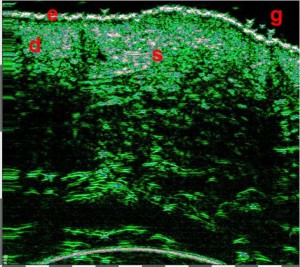

-Υπέρηχος Υψηλής Συχνότητας (HFUS) και Ιστολογία

Εφαρμογές δερματολογίας

-Κύριες εφαρμογές

-Κύριες παθολογικές διεργασίες

-Διαφοροποίηση μεταξύ υπερτροφικών και χηλοειδών ουλών

-Διάγνωση μορφών ακμής